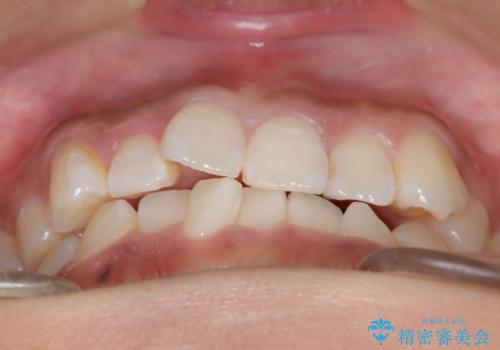

- 前歯の叢生(がたつき)を主訴に来院された患者様です。以前マウスピース矯正をされていたそうでしたが、自身での継続が難しいことなどを理由に、ワイヤー矯正にて改めて矯正治療を希望されました。非抜歯にて治療を計画し治療を行いました。

歯の動きが良く、スムーズに治療を終了しました。一般的にワイヤー矯正はブラッシングが難しいのですが、毎回一生懸命セルフケアをされていたのが印象的です。治療においては、歯の衛生状態も一緒にチェック致します。